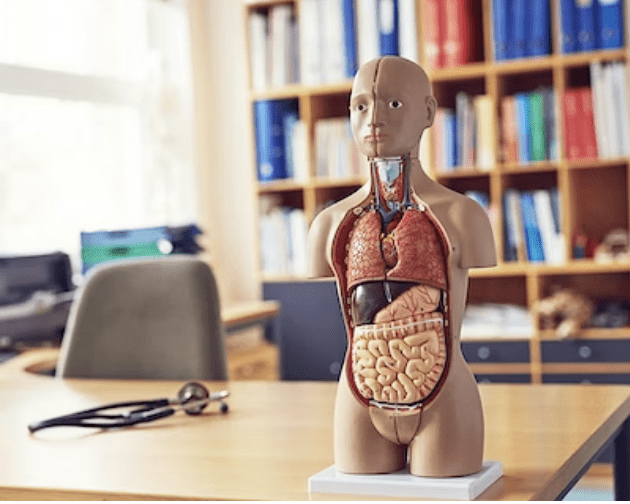

Anatomisk modell av det sympatiska nervsystemet

Anatomisk modell som illustrerar det sympatiska nervsystemet, sett i relief från höger sida av kroppen. Modellen är särskilt detaljerad kring plexus cardiacus och plexus sacralis.

Modellen väger 4,3 kg och följande mått

- Längd: 10 cm

- Bredd: 25,5 cm

- Höjd: 74 cm

Modellen levereras fast monterad på grönt underlag